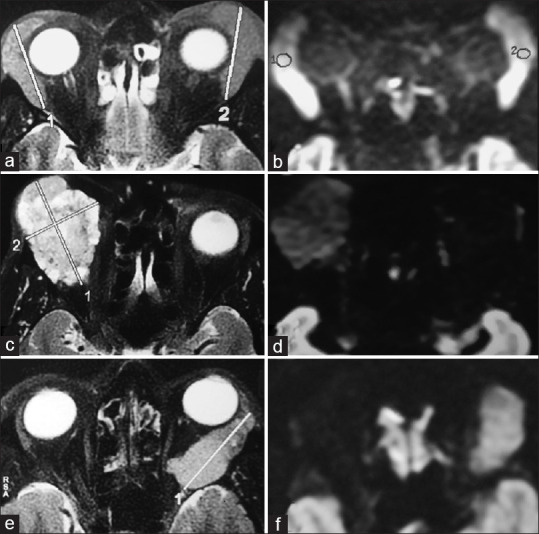

目的:旨在分析眼眶病变的放射学诊断及其与最终组织病理学结果的相关性。我们比较了外部放射科医生和内部专门从事眼眶成像的放射科医生的初步报告,以评估眼眶成像诊断的准确性:这是一项回顾性病历审查,对象是 7 年间转诊到南印度一家三级眼科医疗中心的 40 名患者。这些患者已经在其他地方做了眼眶造影。内部放射科医生重新评估了影像学检查结果。放射学检查结果与组织病理学诊断结果相互关联。比较了两位放射科医生的诊断准确性。计算了两组患者区分恶性和良性病变的敏感性、特异性、阳性预测值(PPV)和阴性预测值。分析了两组放射诊断对肿瘤性和炎症性病变的敏感性和 PPV:本院放射科医生和院外放射科医生区分恶性病变和良性病变及炎症性病变的准确率分别为 95% (κ = 0.9 [0.764, 0.997])和 50% (κ = 0.036 [-0.160, 0.232])。本院放射科医生对良性病变的放射诊断灵敏度和 PPV 分别为 93.31% 和 100%,对恶性病变的灵敏度和 PPV 分别为 95.24% 和 95.24%。相反,外部放射科医生的报告显示,良性病变的敏感性和 PPV 分别为 76.92% 和 66.67%,恶性病变的敏感性和 PPV 分别为 14.28% 和 60%:结论:如果由在眼眶成像方面经验丰富的放射科医生进行分析,放射诊断的准确性会很高。

Purpose: The objective is to analyze the radiological diagnosis of orbital lesions and their correlation with the final histopathological findings. We compared the initial reports by extramural radiologists and an in-house radiologist specialized in orbital imaging to evaluate the diagnostic accuracy in the interpretation of orbital imaging.

Methods: This was a retrospective chart review of forty patients referred to a Tertiary Eye Care Center in South India over a period of 7 years. These patients already had their imaging done elsewhere. The imaging was re-evaluated by an in-house radiologist. The radiological findings were correlated with the histopathological diagnosis. The diagnostic accuracy between the two radiologists was compared. The sensitivity, specificity, positive predictive value (PPV), and negative predictive value in differentiating malignant from benign lesions were calculated in both groups. The sensitivity and PPV of the radiological diagnosis for neoplastic and inflammatory lesions in both groups were analyzed.

Results: The accuracy in differentiating malignant from benign and inflammatory lesions by our in-house radiologist and extramural radiologists was 95% (κ = 0.9 [0.764, 0.997]) and 50% (κ = 0.036 [-0.160, 0.232]), respectively. The sensitivity and PPV of the radiological diagnosis by our in-house radiologist were 93.31% and 100% for benign lesions and 95.24% and 95.24% for malignant lesions. On the contrary, reports from the extramural radiologists showed a sensitivity and PPV of 76.92% and 66.67% for benign lesions and 14.28% and 60% for malignant lesions.

Conclusion: A high radiological diagnostic accuracy is possible when analyzed by radiologists experienced in orbital imaging.